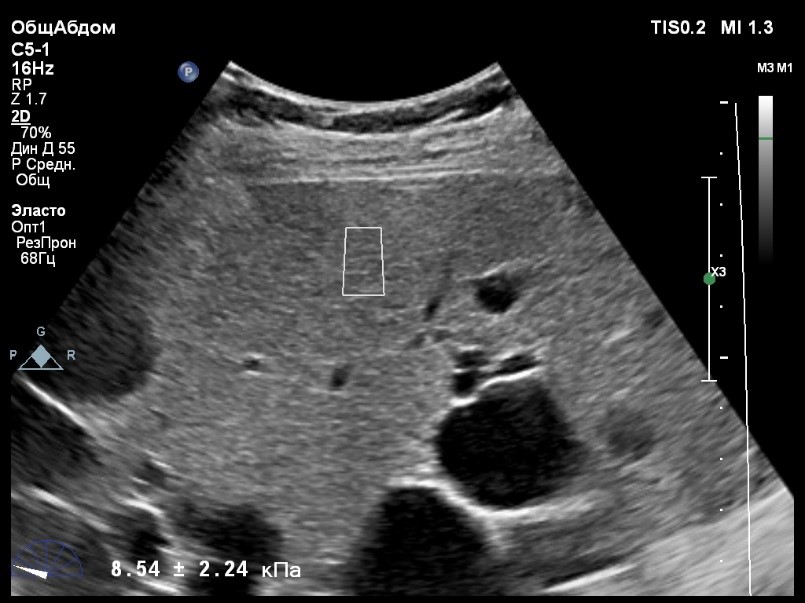

Пациент обратился к доктору с направлением на исследование степени жесткости печени в июне 2017 года. Из истории болезни, пациент страдает Гепатитом С с 2014 года. Лечение не получал. Транзиентная эластография показала не коррективные значения степени жесткости печени по причине сопутствующего поликистоза печени. На момент настоящего исследования, пациент не принимал пищу на протяжении 4 часов, АСТ, АЛТ не превышают патологических значений. Для оценки жесткости была выбрана технология компании Philips ElastPQ (точечная эластография) и прибор компании Philips Epiq 7 Исследование было проведено в соответствии с клиническими рекомендациями для ультразвуковых приборов компании Philips. В результате исследования были получены следующие результаты:

| 1 [7.95] kPa | 2 [8.73] kPa | 3 [8.11] kPa |

| 4 [9.32] kPa | 5 [8.05] kPa | 6 [9.52] kPa |

| 7 [8.66] kPa | 8 [7.36] kPa | 9 [8.54] kPa |

| 10 [8.30] kPa | 11 [6.56] kPa | 12 [7.14] kPa |

| 13 [7.47] kPa | 14 [6.56] kPa | 15 [6.56] kPa |

Стандартное Отклонение [0.85] kPa Медиана Жесткости [8.05] kPa Фактор Качества IQR/Med 10%

Зона интереса расположена на более чем на один сантиметр глубже капсулы, параллельно ходу луча, в середине изображения, в участке печени лишенном кист.

Капсула видна как белая линия перпендикулярная ходу ультразвукового луча, исследования производятся приблизительно в одном и том же сегменте печени.

Стандартное отклонение (2,26 kPA) не превышает 30 процентов от полученного значения (8,54 kPA).

Для интерпретации полученных клинических данных были использованы Рекомендации по проведению эластографии сдвиговой волной для оценки жесткости печени при использовании ультразвуковых аппаратов компании Филипс с примером протокола. Техническая сложность проведения слепой эластометрии печени связана с сопутствующим поликистозом органа и диагностическим методом выбора в данной ситуации является Эластография с возможностью визуального контроля положения контрольного объема. Подготовка пациента соответствовала проводимому исследованию. Представленные слайды проведенного исследования свидетельствуют о правильном техническом исполнении проб, отсутствием в поле контрольного объема кистозных образований, что позволяет заключиться о достоверности полученных измерений. Таким образом, учитывая полученную медиану жесткости на уровне 8,05 кРа (6.56 – 9.52 kPa) и уровень стандартных отклонений не превышающих 30%, полагаю, что уровень степени фиброза соответствует стадии F2. Заведующий отделением УЗД МЦ «Асклепий», Глушенко Д. Е.